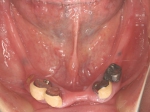

二次オペ時(鏡像)